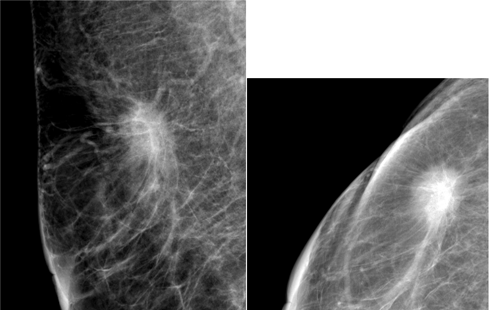

The aim of this research is to describe the intrinsic subtypes of breast cancer which has an appearance of spiculated mass on mammography. There were 59 patients that met the inclusion criterions at DR. Soetomo General Hospital, Surabaya between January 2017 and December 2018 (Figure 1−4). The youngest subject is 34 years old and the oldest being 73 years old with the average age of 52.1 years old. We divided the patients into three age groups, below 40 years old, 40-50 years old and above 50 years old. The average age of subtype Luminal A were the oldest with 53.6 years old, 52.9 years old in Luminal B, 47.4 years old in the basal-like and the youngest of which 46.8 years old in the HER2+subtype (Table 1) (Figure 5).

Figure 3 The mammographic appearance of spiculated mass in subject with pathological subtype Luminal C.

Figure 4 The mammographic appearance of speculated mass in subject with pathological subtype Luminal D.